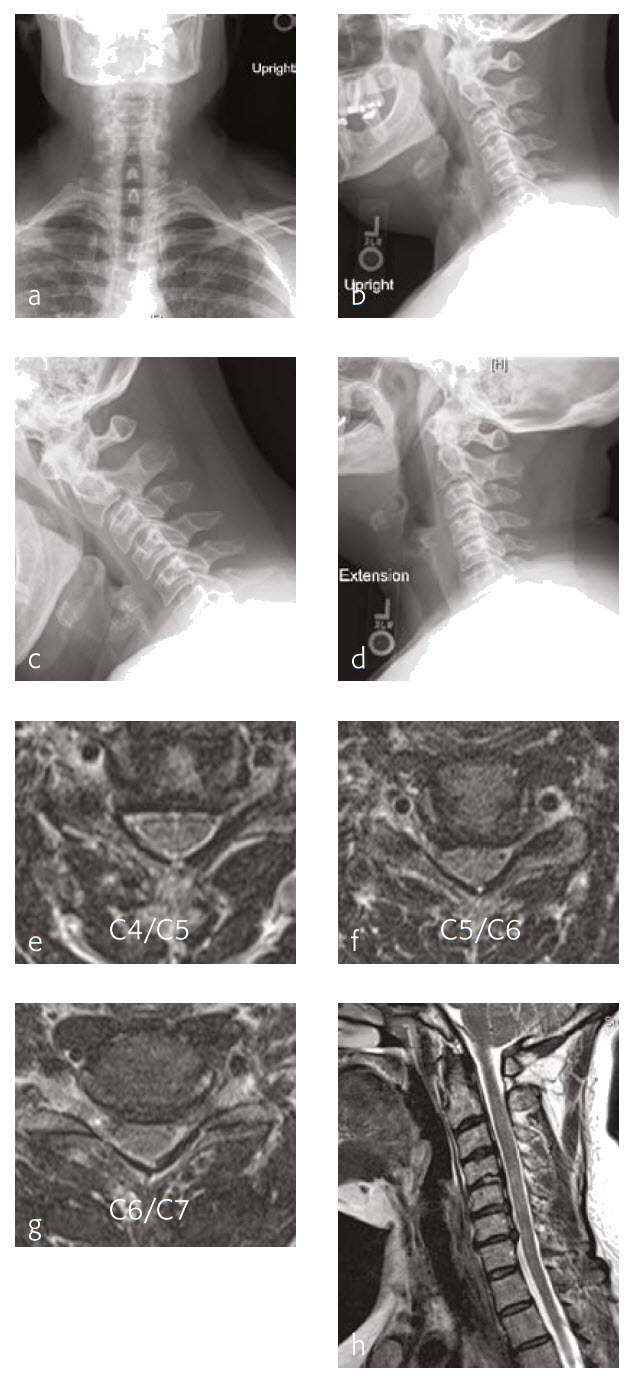

Case 2: Neck pain with cervicogenic headaches

The patient works at a grocery store as a produce stocker and has a history of C5 through C7 ACDF done in 2005 (Fig 3). Her symptoms were relieved at that time, but she had quite severe neck pain and bilateral radicular symptoms. She had chronic C6 radiculopathy since recovery from that procedure, however, was able to return to work. Unfortunately, over the last 34 months, she has had a recurrence of symptoms, with constant neck pain and occasional cervicogenic headaches.

She will occasionally get bilateral pain, a pins and needles-type sensation through a number of distributions, including C5 through her shoulders, less occasionally through a C7 or C6 distribution. Movement of her neck was becoming increasingly painful, particularly with flexion and lateral flexion to the right and left.

She has tried a number of conservative modalities including narcotic pain medications, rest, heat, ice, physical therapy-type exercises, activity avoidance, and oral steroids. She states that she has had a steroid injection. These were not helpful for her. Eventually, she got an MRI and was found to have adjacent level disease.

On manual muscle testing, the patient had 5/5 strength bilaterally with shoulder abduction, elbow extension and flexion, wrist extension and flexion, finger abduction and grip strength.

The patient has appropriate range of motion through her cervical spine with flexion and extension, and lateral flexion and rotation. She gets grimacing pain with extreme ends of flexion as well as bilateral rotation and lateral flexion. She has no tenderness to palpation of the spinous process or paraspinous musculature of her cervical spine. She has decreased sensation in bilateral C5 distributions.

Follow-up (6 months)

The patient is now about 6 months status post a C4-C5 discectomy and interbody fusion with removal of preexisting C5 screws (Fig 4). She was recovering well and has not been taking any narcotic pain medication. She takes acetaminophen.